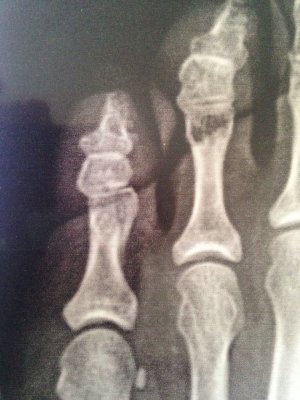

Здравствуйте! 28 декабря ударилась об угол кровати. Рентген показал косой перелом дистального отдела проксимальной фаланги 5 пальца стопы. Врач сказал, что смещение минимальное. Предложил гипсовую лангетку, но я отказалась, тогда дал жёсткую штучку и сказал обрезать по форме стопы, привязать и ходить на пятке. Прошло больше 3 недель, сделала контрольный снимок (прилагаю), врач утверждает, что всё хорошо, процесс срастания идёт, сказал надо ещё 10 дней ходить с фиксацией.

1. Действительно ли по снимкам нет смещения?

2.я, сравнивая первые снимки и после 3 недель не вижу никакого прогресса в сращении..Он есть?